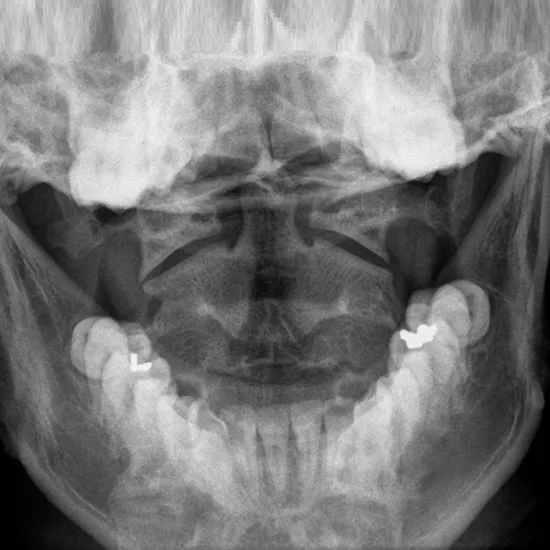

The open mouth(odontoid) view radiograph (x-ray) of the cervical spine is recommended to evaluate the existence of an upper cervical spine injury such as Dens Fracture, Jefferson's Fracture, Transverse Ligament Injury Basilar Invagination, etc.